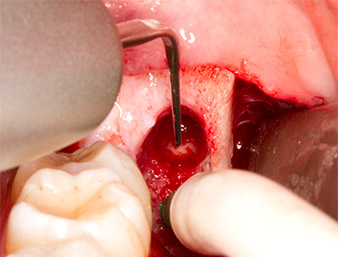

A continuación, se utilizó un inserto para la retirada de los sedimentos periodontales (Piezomed P1) y se amplió mínimamente el surco periodontal del resto radicular (figura 8).

El mismo inserto activado se introdujo en el canal radicular y aflojó el fragmento gracias a sus vibraciones microoscilantes (figuras 9 y 10).

Piezomed P1

Imagen 9: El fabricante recomienda el inserto Piezomed P1 sobre todo para la extracción periodontal de placa, pero también resulta adecuado para propósitos quirúrgicos. En este caso, se colocó en el canal radicular después de una ampliación mínima del surco periodontal.

Imagen 10: Gracias a su estilizado diseño, el inserto puede introducirse en el canal radicular para retirar el resto radicular mediante microoscilaciones (vibraciones).

A continuación, se utilizó el accesorio P1 para retirar de una pieza el resto radicular de aproximadamente seis milímetros de longitud (figura 11).

El tejido inflamatorio periapical se retiró también con sumo cuidado utilizando un excavador manual. La figura 12 muestra el alvéolo vacío con el nervio alveolar inferior expuesto.

radicular extraído

Imagen 11: El resto radicular extraído medía más de 6 milímetros.

Nervus alveolaris inferior

Imagen 12: En la profundidad del alvéolo se distingue el nervio alveolar inferior.

Ampliación del surco periodontal y obtención de virutas óseas

Con el estilizado inserto piezoquirúrgico Piezomed P1, fue posible ampliar de forma precisa el surco periodontal del resto radicular, a modo de preparación para retirarlo fácilmente mediante su introducción en el canal radicular. También en este caso se demostró que el funcionamiento microoscilante resultaba una gran ventaja y que el uso flexible era evidente. Frente a esto, los instrumentos rotativos no ofrecen ninguna opción similar.